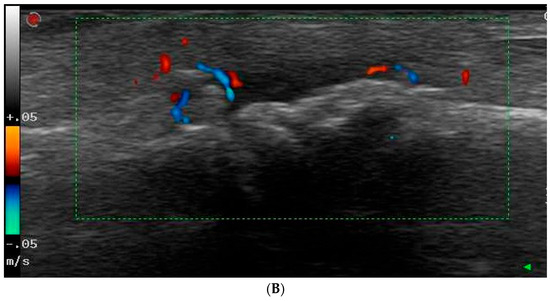

2.3. Ultrasonography Examination